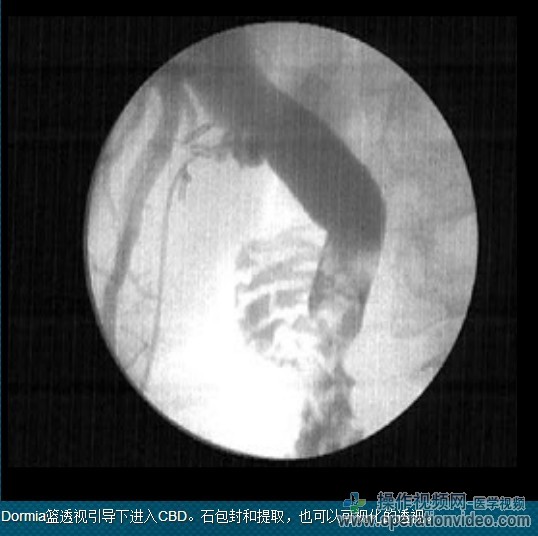

-引进的Dormia篮通过操作通道(或胆道镜一起)进入CBD。石头检索,由Dormia购物篮针对所述内窥镜的前端牢固地保持

胆道镜与Dormia篮子在持续的视图被撤回。